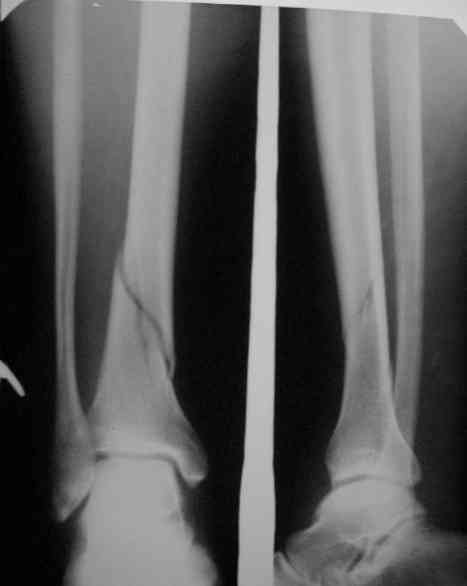

Здравствуйте коллеги!Больной 29 лет поступил 1 мая с Диагнозом: Закрытый спиральный перелом н/3 большеберцовой кости, перелом в/3 малоберцовой.

На пятые сутки выполнен вот такой остеосинтез (см R-gr) . На сегодня мы имеем перелом нижнего винта, замедленное сращение( R- gr от 11.09.06) Больного ничего не беспокоит, ходит с костылями с ограниченной нагрузкой. На наш взгляд возможно обойтись :1 Удаление сломанного винта и верхнего блокирующего с последующим более глубоким погружением штифта и его дистальным блокированием. Либо замена на более длинный (Экперт-Синтез).2 Остеотомия косая малоберцовой кости.С большим вниманием выслушаем возможные варианты, тактики в таком случае.С Уважением Владимир Бахарев.P.S Извинямси за качество снимков!

Но вопрос тут не столько в типе штифта (практически все доступные удержат дистальный отломок такой длины, и более дорогой стержень не даст тут выигрыша, адекватного разнице в цене), а в том, как должны располагаться отломки и штифт. Вот с этим в застарелом случае при околосуставном повреждении обычны трудности.

Большого ротационного смещения вроде не видно. IMHO здесь надо бы 1)восстановить длину (дистрактор) - возможно, получится одномоментно.

2)Устранить смешение периферического отломка кнаружи - спереди назад отклоняющие (poller) спицы или винт ввести, чтобы оттеснить штифт к латеральной стенке. Понятное дело, ввести гвоздь дистальнее, чем этот сейчас. Запереть можно сразу динамически.